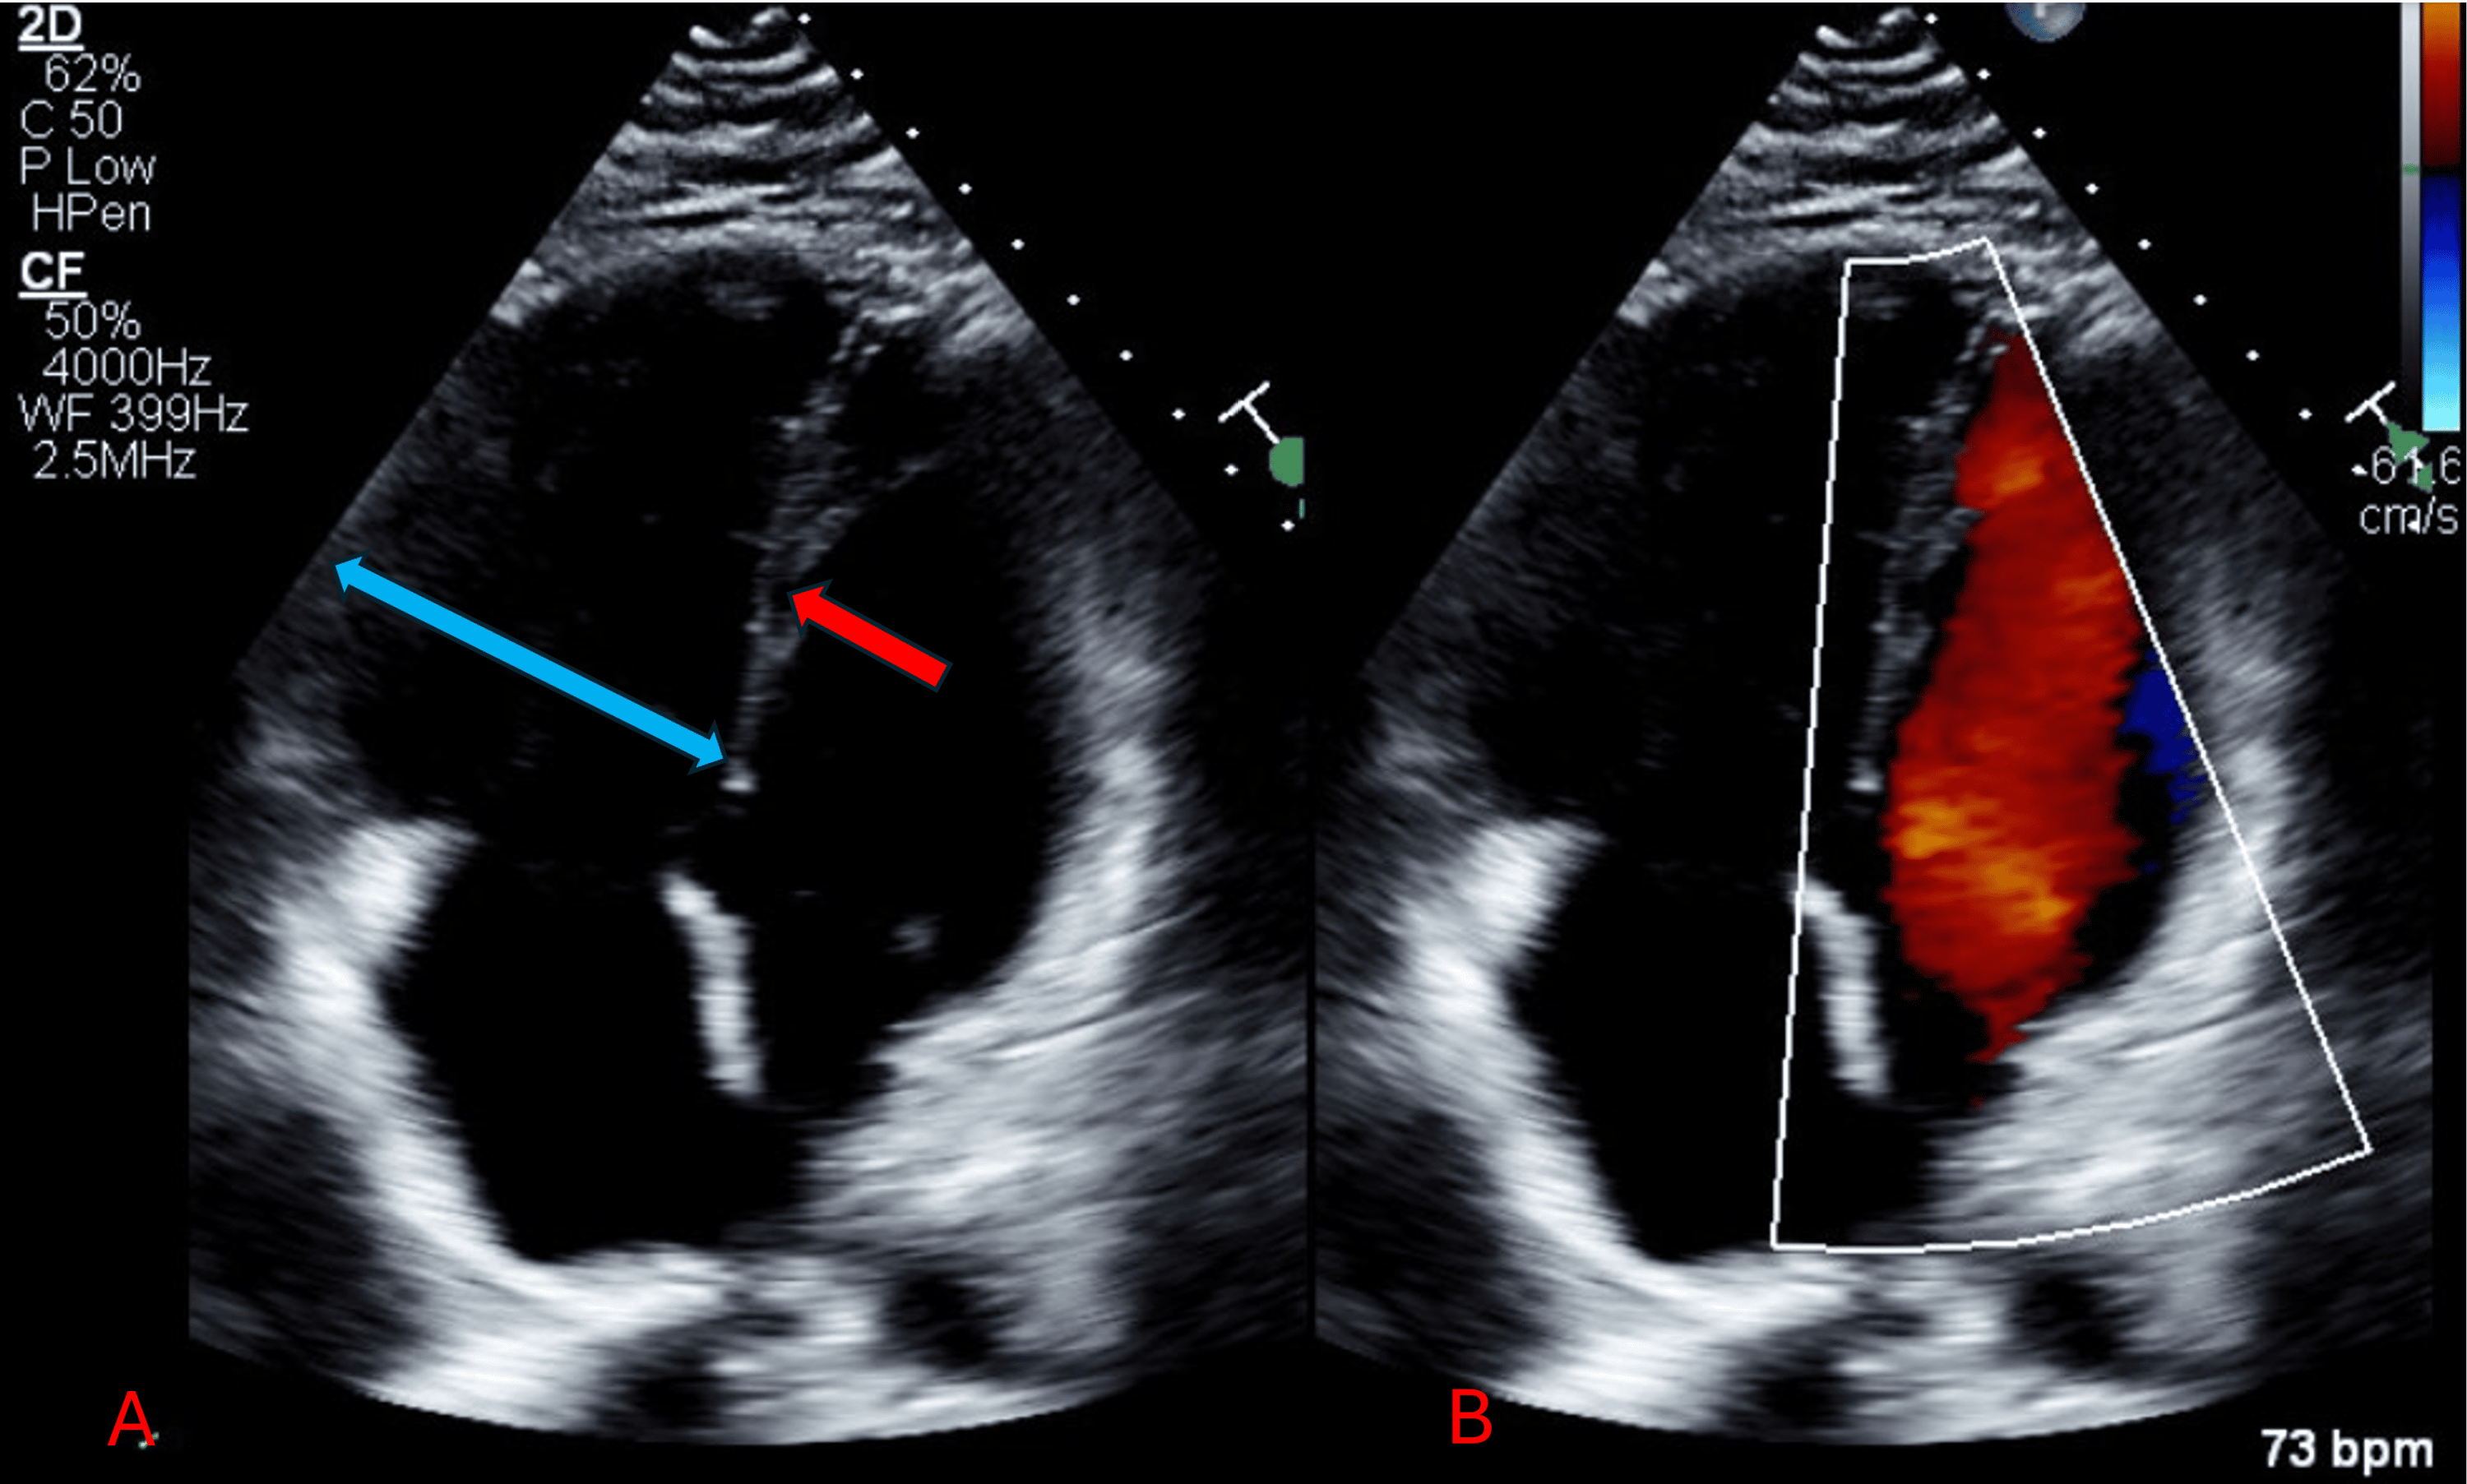

From www.cureus.com

Cureus Protein S Deficiency and COVID19 A Brutal Combination Protein S Deficiency Pulmonary Embolism Free and total protein s deficiency was not associated with venous. Having this deficiency puts you at risk for a blood clot in your leg or arm veins that’s known as a deep vein thrombosis (dvt). Subjects were regarded protein s deficient when protein s levels were <2.5th percentile of the controls. There are several genetic conditions known to increase. Protein S Deficiency Pulmonary Embolism.

Cureus Protein S Deficiency and COVID19 A Brutal Combination Protein S Deficiency Pulmonary Embolism Free and total protein s deficiency was not associated with venous. Having this deficiency puts you at risk for a blood clot in your leg or arm veins that’s known as a deep vein thrombosis (dvt). Protein s deficiency is an inherited thrombophilia associated with an increased risk of thromboembolism. Subjects were regarded protein s deficient when protein s levels. Protein S Deficiency Pulmonary Embolism.

Cureus Protein S Deficiency and COVID19 A Brutal Combination Protein S Deficiency Pulmonary Embolism Subjects were regarded protein s deficient when protein s levels were <2.5th percentile of the controls. Having this deficiency puts you at risk for a blood clot in your leg or arm veins that’s known as a deep vein thrombosis (dvt). There are several genetic conditions known to increase the risk of vte including factor v leiden, prothrombin gene mutation. Protein S Deficiency Pulmonary Embolism.